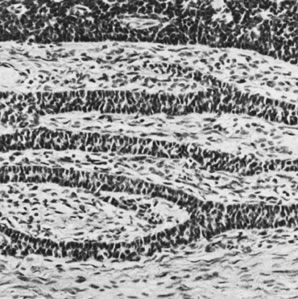

The gonadoblastoma is a hamartomatous neoplasm composed of germ cells, sex cord derivatives, and, in two thirds of the cases, stromal derivatives resembling lutein cells and Leydig cells without crystals of Reinke.76 The germ cells are similar to those of the ovarian dysgerminoma and testicular seminoma, and the sex cord elements have the appearance of immature Sertoli or granulosa cells. In one case, bundles of Charcot-Böttcher filaments, more or less specific for Sertoli cells, were identified in the sex cord element of a gonadoblastoma. The germ cells and sex cord derivatives grow characteristically in sharply demarcated aggregates, in which the most common pattern is one of germ cells distributed among more numerous smaller sex cord elements. The latter are typically oriented around hyaline bodies, creating a microfollicular appearance. The hyaline bodies are composed of dense basement membrane material, which is occasionally observed to be continuous with the basement membranes surrounding the discrete aggregates. Foci of calcification, which typically appear first in the hyaline {bodies,} are present in most of the cases and often become confluent (Fig. 33). The calcification may be so extensive that it is recognizable on an x-ray film of the pelvis or abdomen. In approximately half the cases, the germ cells abandon the discrete aggregates to invade the stroma, forming a germinoma (dysgerminoma or seminoma). Occasionally, a more highly malignant form of germ cell tumor, such as a yolk sac tumor, choriocarcinoma, or embryonal carcinoma, develops in association with a gonadoblastoma. The gonadoblastoma may be microscopic or may form a large mass, which can be soft, fleshy, and cream colored in the presence of overgrowth by germinoma; yellow and extensively calcified; or of mixed color and consistency.

Fig. 33. Gonadoblastoma with calcification (magnification, ×130).(Serov SF, Scully RE, Sobin LH: Histological Typing of Ovarian Tumours. Geneva, World Health Organization, 1973.)

Although the gonadoblastoma without an associated malignant germ cell tumor has not been shown to metastasize and can be regarded as an in situ form of malignancy, the common development of invasive germinoma (Fig. 34) and the occasional association of more virulent forms of germ cell tumor indicate that a gonad containing a gonadoblastoma is a potential hazard to the patient and should be removed. Because the tumor is bilateral in more than one third of the cases and almost always develops in a patient with abnormal gonads, the removal of the contralateral adnexa is also indicated in almost every case, even though neoplastic involvement is not evident at the time of operation. Because many gonadoblastomas have not been palpable on pelvic examination and have been incidental findings during an operation to determine the nature of a sexual disorder, and because patients with gonadal dysgenesis and a Y chromosome have been reported to harbor gonadoblastomas or other malignant germ cell tumors in approximately one quarter of the cases, routine gonadectomy is indicated in cases of gonadal dysgenesis with a Y chromosome. Although no large series of cases of malignant germ cell tumors arising in gonadoblastomas has been reported with adequate follow-up data, germinomas originating in gonadoblastomas are capable of metastasis, and the occasionally associated more malignant forms of germ cell tumors have been shown to exhibit a malignant behavior similar to that of the same types of tumor occurring in otherwise normal patients.

Fig. 34. Gonadoblastoma with dysgerminoma (magnification, ×160).(Serov SF, Scully RE, Sobin LH: Histological Typing of Ovarian Tumours. Geneva, World Health Organization, 1973.)